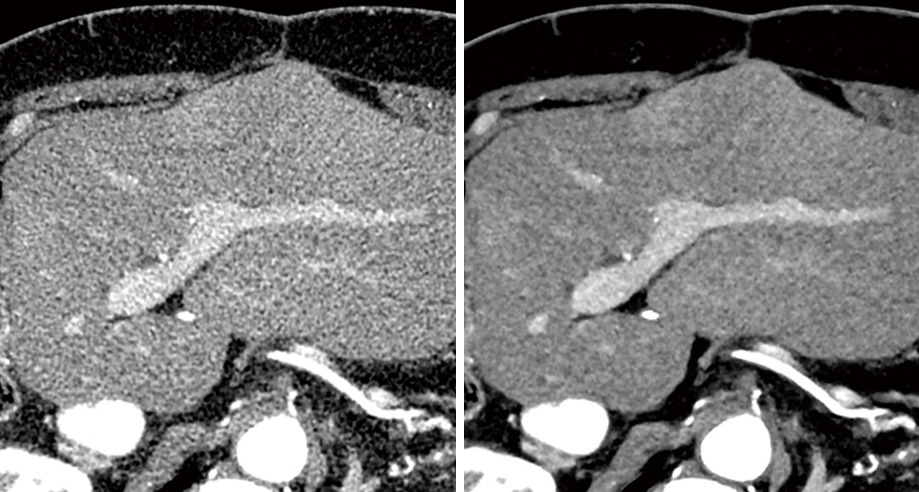

従来CT画像と低線量で撮影した胸部ファントムの比較画像

従来技術(左)と、「Advanced intelligent Clear-IQ Engine (AiCE)」(右)による画像の比較。

ざらついたノイズが低減され、高画質を実現。